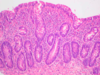

Normal Colon